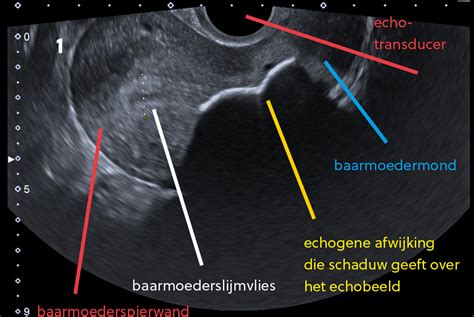

Echo-onderzoeken tijdens de zwangerschap

De 13-weken echo

De 13-weken echo is een onderzoek dat vroeg in de zwangerschap wordt uitgevoerd om te screenen op een aantal aangeboren afwijkingen bij de baby. Hierbij wordt onder andere gelet op de correcte ontwikkeling van de rug en schedel. Dit onderzoek brengt geen risico's met zich mee voor moeder en kind, maar biedt geen garantie op een gezonde baby, aangezien niet alle afwijkingen zichtbaar zijn op de echo. De financiering van de 13-weken echo valt onder een landelijke subsidieregeling.

De 20-weken echo

De 20-weken echo, ook wel structureel echoscopisch onderzoek (SEO) genoemd, onderzoekt het kindje op mogelijke aangeboren afwijkingen. Er wordt gekeken naar de ontwikkeling van de ruggengraat, schedel, organen, de groei van het kindje en de hoeveelheid vruchtwater. Net als de 13-weken echo brengt dit onderzoek geen risico's met zich mee en biedt het geen absolute garantie op een gezond kind. De financiering van de 20-weken echo wordt ook gedekt door een landelijke subsidieregeling.